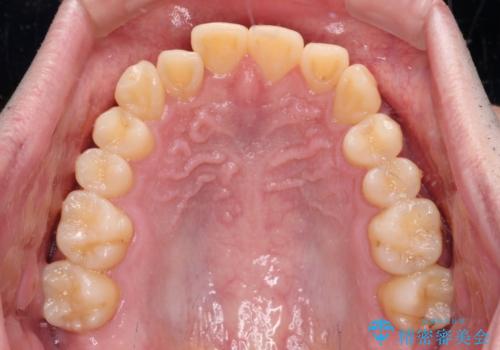

【モニター】前歯のデコボコとクロスバイト ワイヤー矯正で短期間に仕上げる

- 前歯のデコボコとクロスバイトを気にして来院された患者様です。

インビザラインでもワイヤー装置でも矯正治療は可能でしたが、煩わしい自己管理なしに短期間で治療を行いたいとのことで、目立たないワイヤー装置にて治療を行うこととしました。